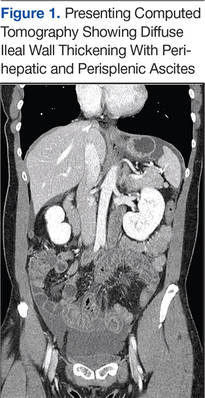

Six weeks after her initial presentation, the patient presented to the ED for the third time with the same symptoms. A CT scan again displayed diffuse ileal wall thickening with significant ascites; slightly worse than the image from initial presentation (Figure 3).